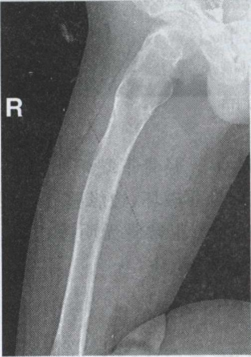

28.男,33岁。右髋痛半年,如图,最可能的诊断为()